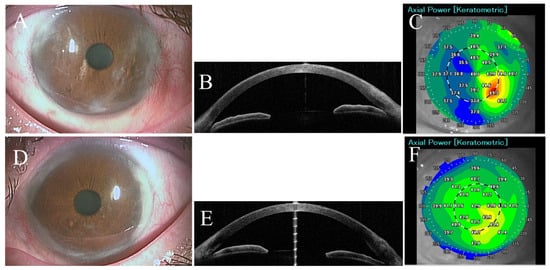

The patient was followed every 2–3 months, and her condition was stable without any recurrence or deterioration in the ocular findings until her last visit in December 2023. The last follow up picture of her eyes shown in (Figure 2) and her last BCVA was 1.2 in right eye (refraction was +4.0 D sphere, −2.0 D axis 150) and 1.2 in left eye.

Figure 1. Slit lamp pictures of right (A) and left (E) eyes of the first case (first visit) showing circumferential corneal infiltrations and pseudopterygia extending from the temporal and nasal sides. Anterior segment optical coherence tomography revealed pseudopterygium and mild corneal thinning in both temporal and nasal sides of right (B) and left (F) eyes. Corneal elevation topography revealed binocular irregular astigmatism in the right and left eyes ((C,G) respectively). Slit lamp pictures of right (D) and left (H) eyes on the first postoperative day.

Figure 2. Slit lamp pictures of right (A) and left (D) eyes of the first case showing the postoperative removal of corneal pseudopterygia from the temporal and nasal sides. Anterior segment optical coherence tomography confirmed the postoperative removal of pseudopterygium of right (B) and left (E) eyes. Postoperative corneal elevation topography revealed binocular improvement in right and left eyes ((C,F) respectively).